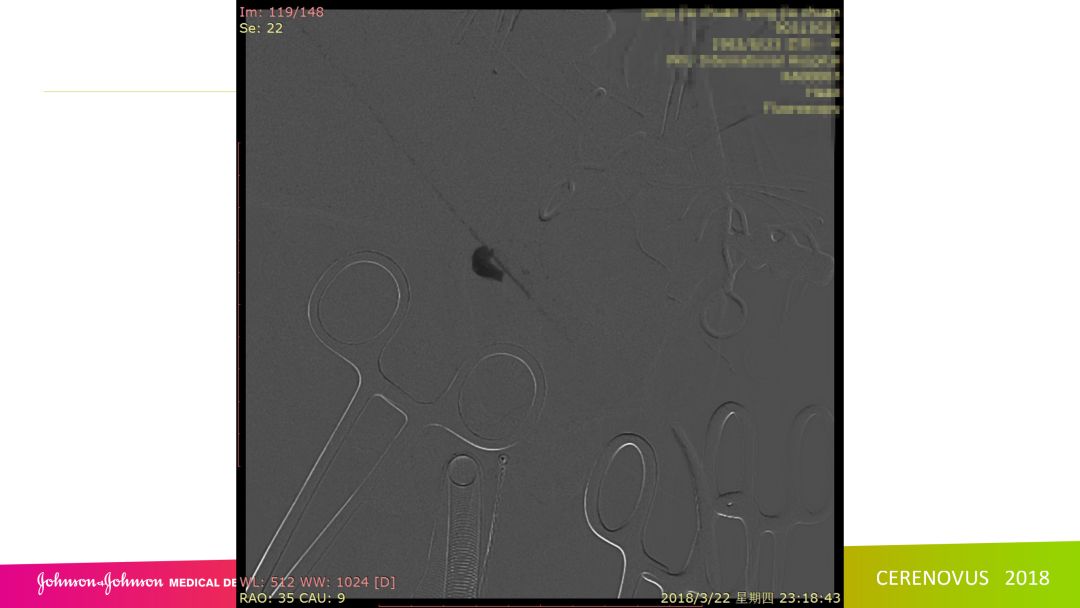

复合手术治疗海绵窦区硬脑膜动静脉瘘一例